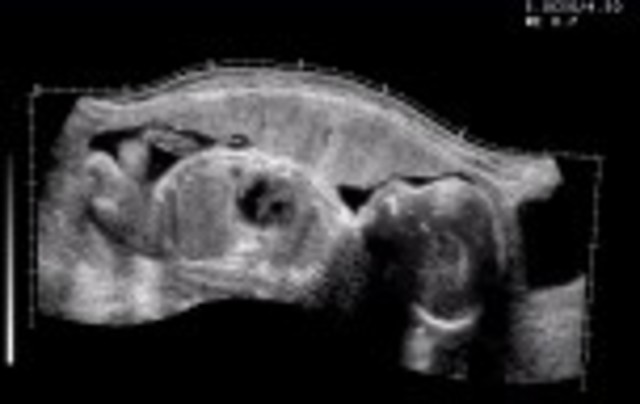

• week 20

week 20

Starts feeling first fetal movements. Heart beat can now be heard.